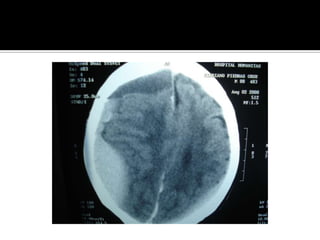

Signos tempranos:  TAC en EVC AgudoSigno dela arteria cerebral media hiperdensaAtenuacion del nucleo lenticularHipodensidad cortical o subcorticalEdema cerebralBorrado de la region insularBorrado de surcos corticalesCompresion ventricularAtenuacion de contraste cortico-medular

Caso clinico Mujer de 20 años , puérpera, llega a Hospital la catalogan como psicosis postparto. Dos días después coma y , después muerte cerebral. La TAC erróneamente fue interpretada como infartos lacunares.

Caso clinico Mujerde 20 años , puérpera, llega a Hospital la catalogan como psicosis postparto. Dos días después coma y , después muerte cerebral. La TAC erróneamente fue interpretada como infartos lacunares.